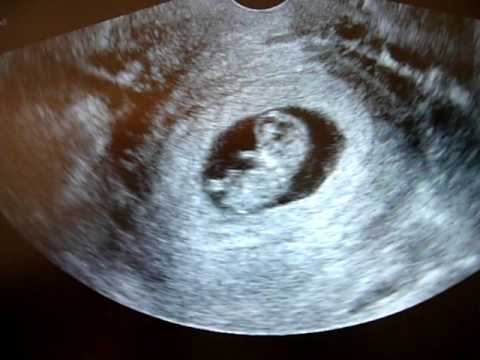

През 10-та гестационна седмица сърцето бие със 160 удара в минута и изтласква кръв до всички органи на бебето. Повечето от органите му вече са формирани и оттук нататък само ще расте. Също така се прегледа положението на плацентата.

това е точно около средата на 3 месец от започването на бременността. Какво се случва с плода на 10 гестационна седмица какво чувства жената Този запис беше проверен от гинеколог-ендокринолог мамолог ултразвуков. През 10 гестационна седмица твоето бебе тежи 4-5 г и е около 5 см.

Този тест се извършва в края на първия триместър обикновено през 12-та гестационна седмица като се измерва количеството течност зад врата на плода за да се изчисли вероятността да страда от тризомия 21 синдром на Даун. Пръстите на крачетата и ръчичките са се разделили и опашката е изчезнала. 10 гестационна седмица Вече можем да говорим за фетус зародиш или плод защото той вече евидим.